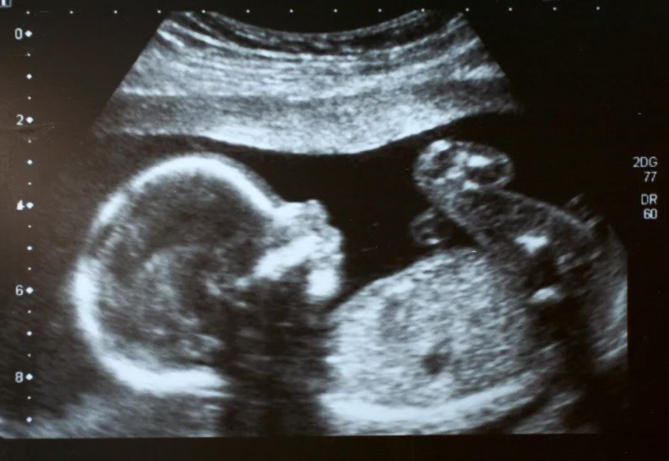

鼻骨是鼻梁的支撑骨骼,在超声图像上表现为一条明亮的短线。有时因为以下原因,可能导致暂时“未显示”:

孕周尚早

胎儿发育有一定规律,如果检查时间偏早,鼻骨骨化可能尚未完成。

宝宝姿势“调皮”

如果胎儿正好面向妈妈脊柱或姿势不利于观察,鼻骨可能被“藏起来”。